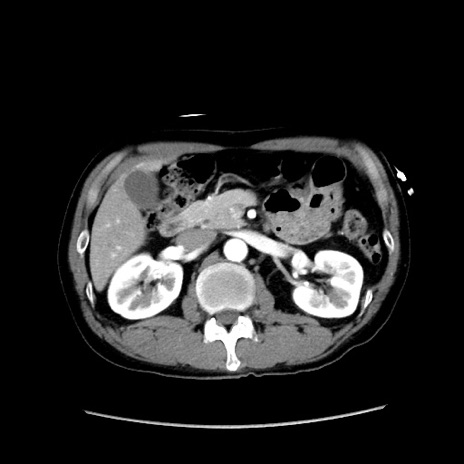

症例37(横断像)

【症例】40歳代 男性

【主訴】腹痛

【現病歴】4時間ほど前に電車に乗車中に臍部上より腹痛出現。徐々に増悪し起立困難となり、救急外来受診。生ものは数日食べていない。今朝お雑煮を食べた。

【身体所見】BT 36.8℃、BP 117/84mmHg、HR 91/min、SpO2 97%、苦悶様、腹部:臍上部広範囲圧痛あり、反跳痛±

【データ】WBC 8100、CRP 0.03